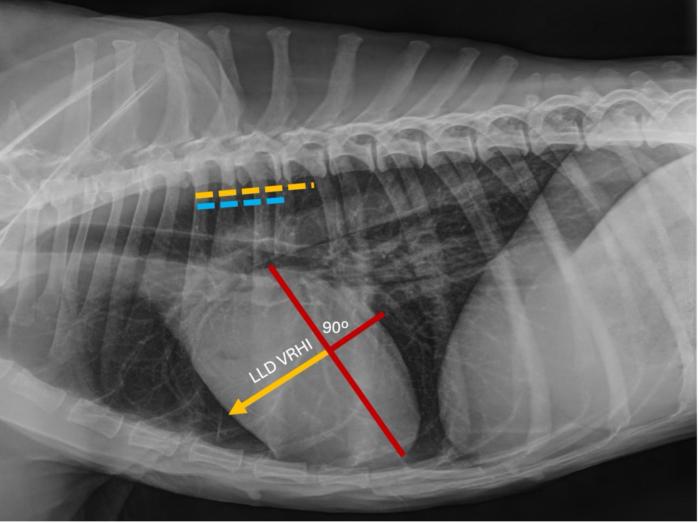

La determinación del VRHi se basó en el protocolo descrito por Puccinelli y colaboradores(2024). En la proyección LLD, el eje largo y el eje corto máximo de la silueta cardíaca se identificaron como se describió previamente para la escala cardíaco vertebral o índice de Buchanan (Buchanan & Bücheler, 1995). En el eje corto, se midió la distancia desde el margen craneal de la silueta cardíaca hasta la línea de intercepción del eje largo. Posteriormente, la misma línea se colocó sobre las vértebras torácicas comenzando en el borde craneal de la cuarta vértebra torácica, y se estimó el número de cuerpos vertebrales (CV). En la vista VD, el eje longitudinal torácico se trazó como una línea superpuesta a la columna vertebral. En el eje transversal, se calculó la distancia desde el margen derecho de la silueta cardíaca hasta el eje longitudinal torácico y se midió contra las vértebras torácicas en las vistas laterales, como se describió anteriormente (Figura 1 y 2).

Representación de la determinación del índice cardíaco vertebral derecho (VRHi) en proyección latero-lateral derecha (LLD) en un perro parasitado por Dirofilaria immitis y que sufría de hipertensión pulmonar. Valor de 3,9 cuerpos vertebrales al trasladar la determinación sobre las vértebras torácicas comenzando en el borde craneal de la cuarta vértebra torácica (línea de color naranja).